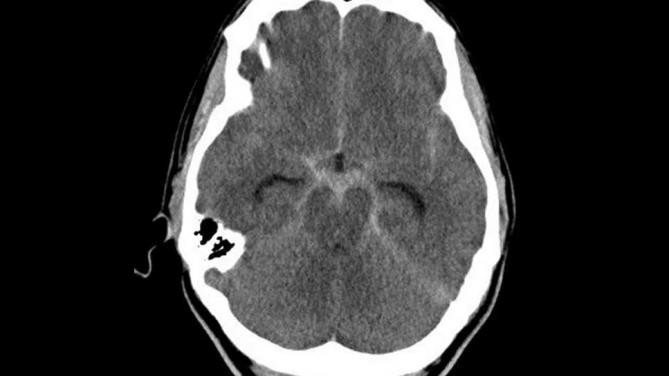

Assinale a alternativa correta a respeito da condição mostrada na imagem a seguir.